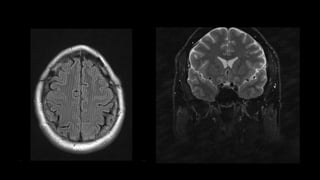

El artefacto de sombreado en la RM se refiere a la pérdida

de intensidad de la señal en una parte de la imagen, lo que

lleva a un sombreado oscuro en esta parte de la imagen.

Causas

• excitación desigual de los núcleos dentro del campo; debido

a los impulsos de RF aplicados en ángulos de giro diferentes

a 90 y 180 grados

• carga anormal de la bobina o acoplamiento de la bobina en

un punto (como en un paciente grande que toca un lado de

la bobina)

• inhomogeneidad en el campo magnético

• Desbordamiento de convertidor analógico a digital

Eje

codificación de frecuencia

codificación de fase